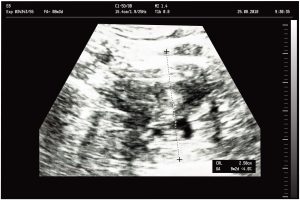

Jedná se o bezbolestné neinvazivní vyšetření, při kterém jsou využívány vysokofrekvenční zvukové vlny (nikoliv ionizující rentgenové záření) k zobrazení tkání lidského těla, a pomocí kterého lékař může určit diagnózu a navrhnout další léčbu. Ultrazvukové vlny procházejí tělem a odrážejí se od jednotlivých orgánů, resp. od přechodů mezi tkáněmi s různou akustickou impedancí. Nevýhodou je neschopnost ultrazvuku projít skrze kost a vzduch, proto je nemožné vyšetřovat např. plíce nebo smyčky na střevech. Při vyšetření je nutné vyvinout dostatečný tlak na měřící sondu kvůli dobrému kontaktu s tělem pacienta, což může být nepříjemné, proto se také povrch sondy pokrývá gelem (EKG krém), aby se zamezilo vzduchovým mezerám mezi sondou a tělem vyšetřovaného. Protože jsou při ultrazvukovém vyšetření tkáně zobrazovány v reálném čase, je možné zachytit strukturu a pohyb jednotlivých orgánů, stejně jako toky krve v cévách.

Přístrojové vybavení a ukázkové snímky: